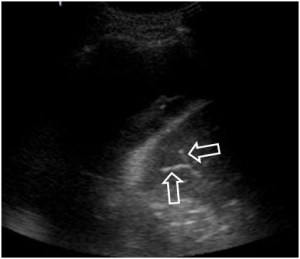

SIGNO DEL BRONCOGRAMA AÉREO

Signo de lesión alveolar visible tanto en la radiografía de tórax como en la TC y en ecografía que consiste en la presencia de los bronquios llenos de aire (visibles como líneas radiolúcidas -flechas-) rodeados de condensación alveolar. En la imagen vemos este signo en un paciente con carcinoma bronquioalveolar.

Así se ve el signo del broncograma en la TC (a la derecha) . Se trata de un paciente con neumonía en el lóbulo superior izquierdo. El broncograma aparece como una línea radiolucente que se afila y ramifica hacia la periferia, y se encuentra rodeada de condensación alveolar.

En la ecografía (signo del broncosonograma aéreo), el aire en los bronquios se ve hiperecogénico (flechas). Este caso corresponde a un colapso debido a un gran derrame pleural, que es la zona más oscura por encima y a la izquierda del pulmón.